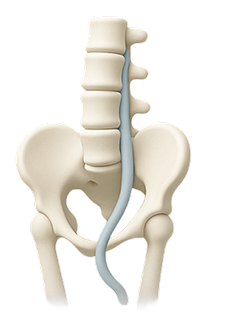

When the soft center of a spinal disc pushes through a crack in the exterior, it can press on nerves and cause pain.

Common Causes of Lower Back Pain

Lower back pain can stem from several underlying issues, including: